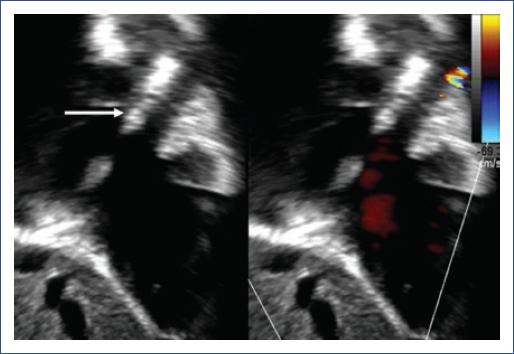

Se presenta el caso de un lactante de sexo femenino de 15 meses de edad, hija de madre con sospecha de lupus eritematoso sistémico, quien contaba con el diagnóstico prenatal de bloqueo auriculoventricular congénito (BAVC). Se decidió la interrupción del embarazo a las 41 semanas de gestación por vía abdominal. Al nacimiento, la paciente presentó frecuencia cardíaca de 55 latidos por minuto. El diagnóstico de BAVC se corroboró por electrocardiograma de superficie. A los 27 días de vida extrauterina se le colocó un marcapasos unicameral St. Jude MicronynMR II (VVI) por presentar datos de bajo gasto cardíaco. A los 15 meses de edad presentó edema bipalpebral. El estudio ecocardiográfico mostró la obstrucción a nivel de la VCS, justo antes de la llegada al sistema ácigos (Fig. 1). La angiotomografía evidenció vena ácigos dilatada, vena hemiácigos tortuosa, así como red venosa tortuosa con colaterales venovenosas en el cuello, que drenaban en su mayoría a la vena ácigos. Se obtuvo imagen sugestiva de trombo de 3.5 mm de diámetro, con obstrucción de más del 50% de la luz del vaso, justo por arriba de la unión de la vena innominada al tronco venoso braquiocefálico derecho y que se continúa hacia la vena ácigos.

Figura 1 Ecocardiograma bidimensional y ecografía Doppler a color, donde se muestra el cable del marcapasos (flecha) y flujo turbulento de la vena cava superior.